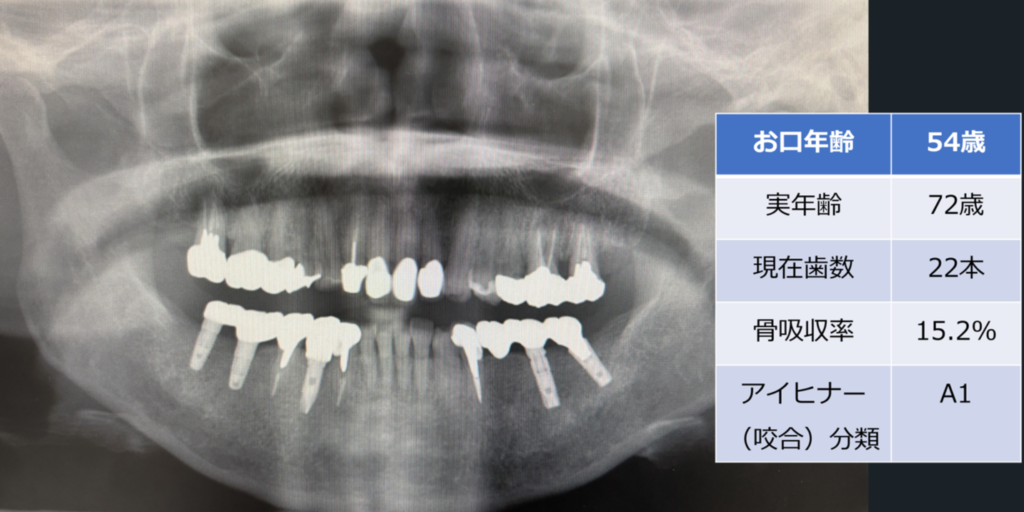

「お口年齢AI」は、歯科パノラマエックス線画像から、現在歯数、インプラント数、アイヒナーの咬合分類、歯槽骨吸収量などの抽出したデータと、生年月日・性別の情報から、「お口年齢」を算出するシステムとなっています。

本システムでは、生活習慣病である歯周病に関連する歯槽骨吸収量も加味して判定しており、また抜歯後にブリッジやインプラント治療を行った場合などは、顕著に「お口年齢」が若年指標として算出されます。